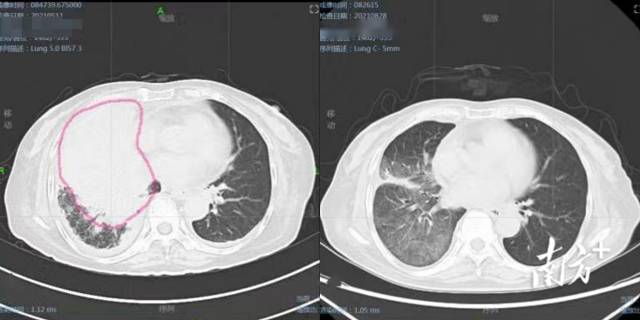

ct显示左肺上叶有支气管内肿块,伴有远端黏液嵌塞,主动脉旁和左支气管